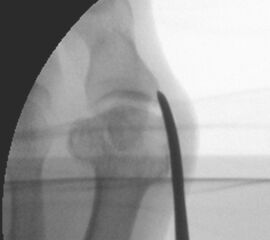

Zum Lesen der Bildbeschreibung und zur Vollansicht bitte die Bilder anklicken.

• Positionierung des Bildwandlers: 90° Winkel zum Os metatarsale I. Benötigt wird die Durchleuchtung des Vorfußes a.p., seitlich und schräg.

Operationstechnik

Die Folge der Operationsschritte sollte strikt von 1. - 4. erfolgen, da ansonsten die mediale Closing Wedge Osteotomie bei vorzeitigem lateralem Release und/oder Akin Osteotomie nicht geschlossen werden kann. Nach der von Isham beschriebenen Originaltechnik finden Implantate keine Anwendung, zur Sicherung und besseren Fixation können osteosynthetische Verfahren angewandt werden (siehe auch Fehler, Gefahren und Komplikationen).